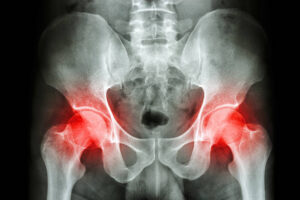

股関節痛とは

股関節痛とは、歩行や立ち上がり、階段の上り下りなど、日常生活に欠かせない動作の際に痛みや違和感を伴う症状を指します。股関節は体の重心を支える大きな関節であり、常に大きな負担がかかるため、一度不調が出ると慢性化しやすく、生活の質を大きく低下させる要因となります。

症状としては、歩行時や立ち上がるときに股関節に痛みが走る、長時間の歩行で鈍い痛みや違和感が出る、関節が固くなり正座やあぐらが難しくなるといったものがあります。

進行すると夜間痛が出て眠れなくなることもあり、さらに腰や膝にまで痛みが広がるケースも少なくありません。